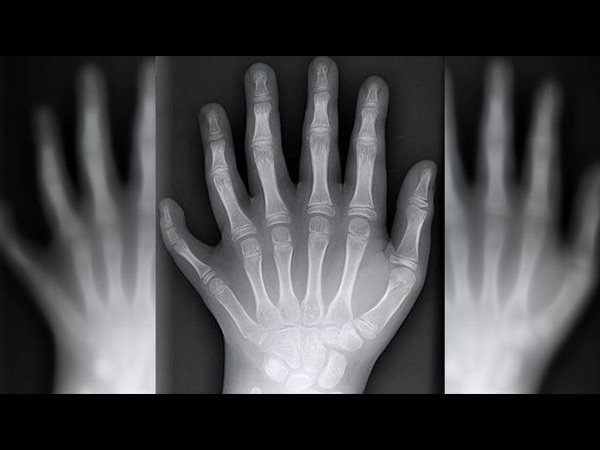

ಈ ಕುಟುಂಬದ ಪ್ರತಿಯೊಬ್ಬ ಸದಸ್ಯನಿಗೂ 12 ಬೆರಳುಗಳು!!

ಕೈ ಮತ್ತು ಕಾಲಿನಲ್ಲಿ ಒಟ್ಟು ಎಷ್ಟು ಬೆರಳುಗಳು ಇದೆ ಎಂದು ಕೇಳಿದರೆ ಆಗ ಬರುವ ಉತ್ತರ 20. ಕೆಲವರಿಗೆ ಒಂದು ಬೆರಳು ಹೆಚ್ಚಿಗೆ ಇರುಬಹುದು. ಆದರೆ ಪ್ರತಿಯೊಬ್ಬ ಮಾನವನು ಒಂದೇ ರೀತಿಯಾಗಿರದೆ ಇಲ್ಲದ ಕಾರಣ ಇದು ಸಹಜವೆನ್ನಬಹುದು. ಮಾನವನ ಗುಣಸ್ವಭಾವದಲ್ಲಿ ಬದಲಾವಣೆಗಳು ಇರುವಂತೆ ದೇಹದಲ್ಲಿನ ಅಂಗಾಂಗಗಳಲ್ಲಿಯೂ ಬದಲಾವಣೆಗಳು ಇರುವುದು. ಕೆಲವರಿಗೆ ಅನುವಂಶಿಯವಾಗಿ ದೇಹದಲ್ಲಿನ ಅಂಗಗಳು ಬಂದಿರುವುದು. ಈ ಲೇಖನದಲ್ಲಿ ಹೇಳಲು ಹೊರಟಿರುವುದು ಬ್ರೆಜಿಲ್ನ ಒಂದು ಕುಟುಂಬದ ಬಗ್ಗೆ ಇಲ್ಲಿರುವ ಸುಮಾರು 14 ಮಂದಿಯ ಕೈ ಮತ್ತು ಕಾಲಿನಲ್ಲಿ ಕ್ರಮವಾಗಿ 12 ಬೆರಳು ಇದೆ. ಇದು ತುಂಬಾ ವಿಚಿತ್ರವೆಂದು ಕಾಣಿಸುವುದಾದರೂ ಸತ್ಯ. ಈ ವಿಶಿಷ್ಟ ಕುಟುಂಬದ ಬಗ್ಗೆ ಮತ್ತಷ್ಟು ತಿಳಿಯಲು ಮುಂದೆ ಓದಿ...

ಈ ಕುಟುಂಬದ ಹೆಸರು ಡಿ ಸಿಲ್ವಾ ಎಂದು. ಕುಟುಂಬದ ವಿಶೇಷತೆಯೆಂದರೆ ಕುಟುಂಬದ 14 ಮಂದಿ ಸದಸ್ಯರು ಹುಟ್ಟುವಾಗಲೇ 12 ಕೈ ಮತ್ತು ಕಾಲಿನ ಬೆರಳುಗಳನ್ನು ಹೊಂದಿದ್ದಾರೆ.

ಅಗ್ರ ಮಾಧ್ಯಮವೊಂದರಲ್ಲಿ ಬಂದಿರುವ ವರದಿಯ ಪ್ರಕಾರ ಇತ್ತೀಚೆಗೆ ಈ ಕುಟುಂಬದ ಜನಿಸಿದ ಸಣ್ಣ ಮಗುವಿನ ಕೈ ಮತ್ತು ಕಾಲಿನ ಬೆರಳುಗಳು 12. ಅನುವಂಶಿಯವಾಗಿ ಬಂದಿರುವ ಈ ಅಸಹಜತೆಯು ಈಗ ಕುಟುಂಬದ ಗುರುತಾಗಿದೆ. ಅಸಹಜತೆ ಬಗ್ಗೆ ಕುಟುಂಬದ ಯಾವ ಸದಸ್ಯನಿಗೂ ಬೇಸರವಿಲ್ಲ.

ಈ ಅನುವಂಶೀಯ ಕಾಯಿಲೆಯು 'ಪಾಲಿಡಕ್ಟೈಲಿ' ಎನ್ನುವ ಪರಿಸ್ಥಿತಿಯಾಗಿದೆ. ಸಾವಿರದಲ್ಲಿ ಒಬ್ಬರು ಇಂತಹ ಪರಿಸ್ಥಿತಿಯಲ್ಲಿ ಹುಟ್ಟುವರು ಎಂದು ಅಧ್ಯಯನಗಳು ಹೇಳಿವೆ.

ಈ ಪರಿಸ್ಥಿತಿಗೆ ವಿವಿಧ ಪರಿವರ್ತನೆಗಳು ಕಾರಣವಾಗುತ್ತದೆ. ಆದರೆ ಕೈ ಮತ್ತು ಕಾಲಿನಲ್ಲಿ ಹೆಚ್ಚುವರಿ ಬೆರಳು ಪಡೆಯುವುದು ಜಿನ್ ಗಳಲ್ಲಿ ಆಗಿರುವ ಕೆಲವು ಪಲ್ಲಟಗಳನ್ನು ಸೂಚಿಸುವುದು. ಸಾಮಾನ್ಯವಾಗಿ ಇದರಿಂದ ಹೆಚ್ಚುವರಿ ಬೆರಳುಗಳು ಬರುವುದು.

ವೈದ್ಯರು ಹೇಳುವ ಪ್ರಕಾರ ನಿಮ್ಮ ತಂದೆ ಅಥವಾ ತಾಯಿಗೆ ಹೆಚ್ಚುವರಿ ಬೆರಳುಗಳಿದ್ದರೆ ನಿಮಗೂ ಹೆಚ್ಚುವರಿ ಬೆರಳು ಬರುವ ಸಾಧ್ಯತೆಯು ಶೇ.50ರಷ್ಟಿರುವುದು.